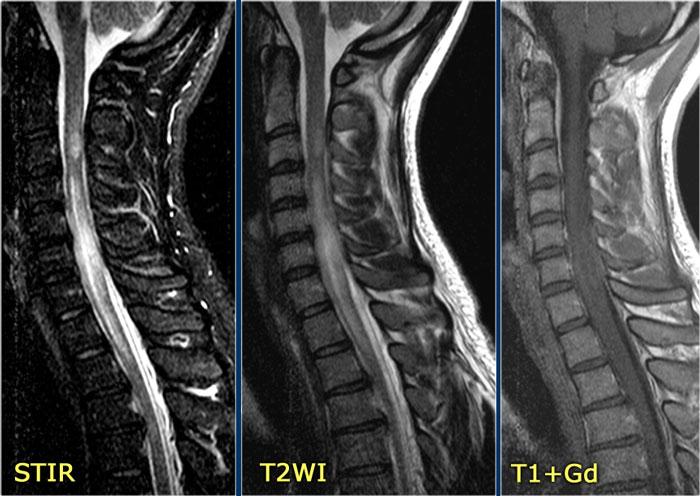

Bên trái là hình ảnh của bệnh nhân nam 60 tuổi mắc u tế bào hình sao.

Bệnh nhân nhập viện với đau vùng ngực và rối loạn cảm giác chi dưới trái, tiếp theo là liệt nửa người trái.

Có tăng tín hiệu đa đoạn trên chuỗi xung T2W kèm phù nề nhẹ, tương tự như hình ảnh đã thấy trong các trường hợp TM.

Trên CE-T1W có vùng ngấm thuốc tương phản từ.

Vùng ngấm thuốc có hình thái nghiêng về u hơn, nhưng việc phân biệt vẫn còn khó khăn.

Như vừa đề cập, chẩn đoán phân biệt chính của các bệnh lý tủy sống đã thảo luận là u tế bào hình sao.

U tế bào hình sao là loại u thâm nhiễm lan tỏa, không có hình thái khối rõ ràng.

Thường có hình ảnh ngấm thuốc không đồng nhất theo từng vùng.

Hình bên trái là u tế bào hình sao ở bệnh nhân 66 tuổi, nhập viện vì các triệu chứng cảm giác tiến triển dần.

Sinh thiết xác nhận chẩn đoán u tế bào hình sao.

Tiếp tục theo dõi hình ảnh tái khám.

Bệnh nhân không có chỉ định phẫu thuật và hình ảnh tái khám cho thấy bệnh tiến triển.